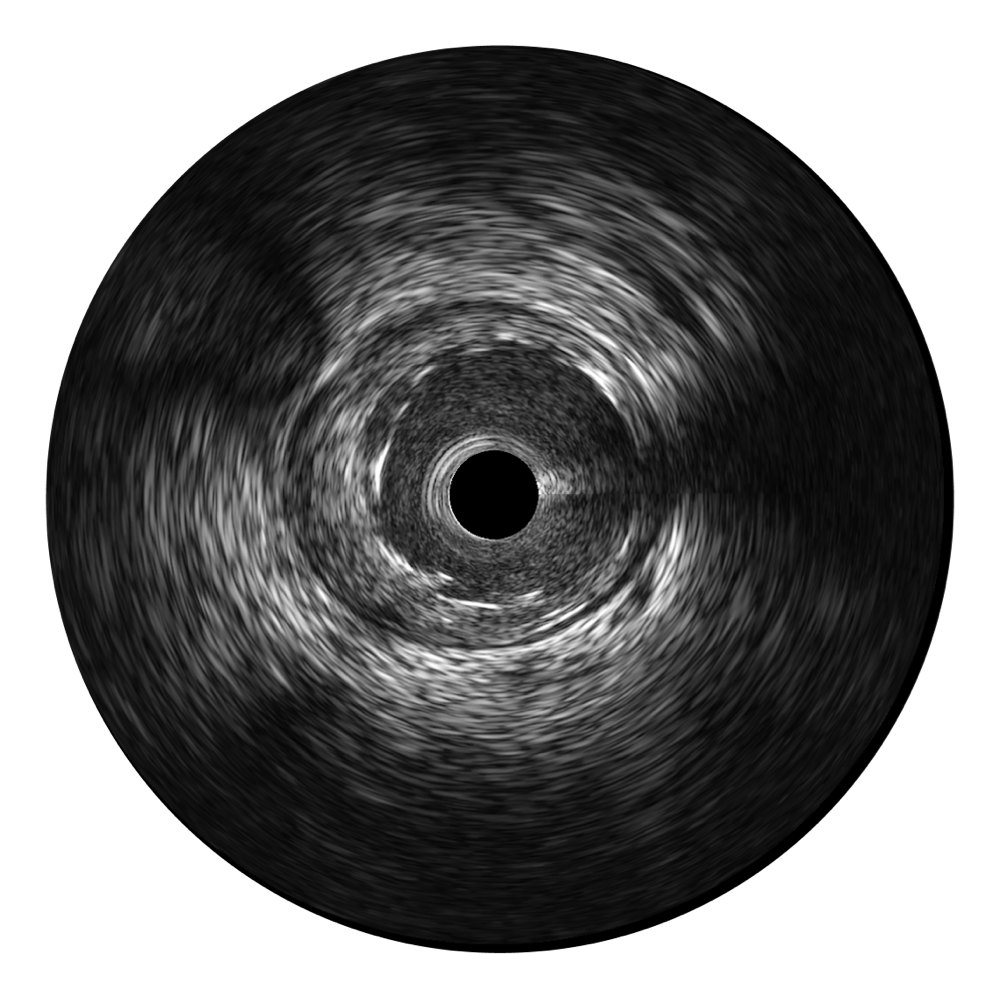

開立超寬頻成像技術(shù)覆蓋20-80MHz1或20-90MHz2頻率范圍, 提供優(yōu)異的分辨力同時也保證充足的穿透深度

對比傳統(tǒng)IVUS導(dǎo)管成像,開立寬頻IVUS圖像的近場支架梁顯影更細(xì)膩,遠(yuǎn)場中膜外血管仍清晰可辨,兼顧遠(yuǎn)中近,兼顧分辨力與穿透深度